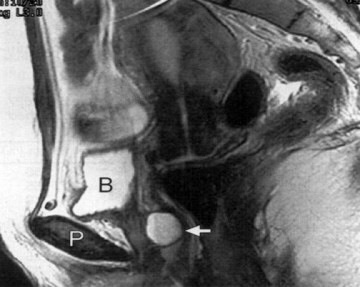

Вот еще немного нашла :,,УЗИ позволяет выявить как кисты, так и дивертикулы уретры. Однако дифференциальная диагностика этих заболеваний без визуализации устья дивертикула невозможна. Тем не менее, при обнаружении жидкостного образования, расположенного кзади от мочевого пузыря или ниже его, следует учитывать возможность наличия дивертикула уретры (Рис. 4 - многокамерный дивертикул проксимального отдела уретры с наличием соустья с просветом уретры ниже шейки мочевого пузыря)